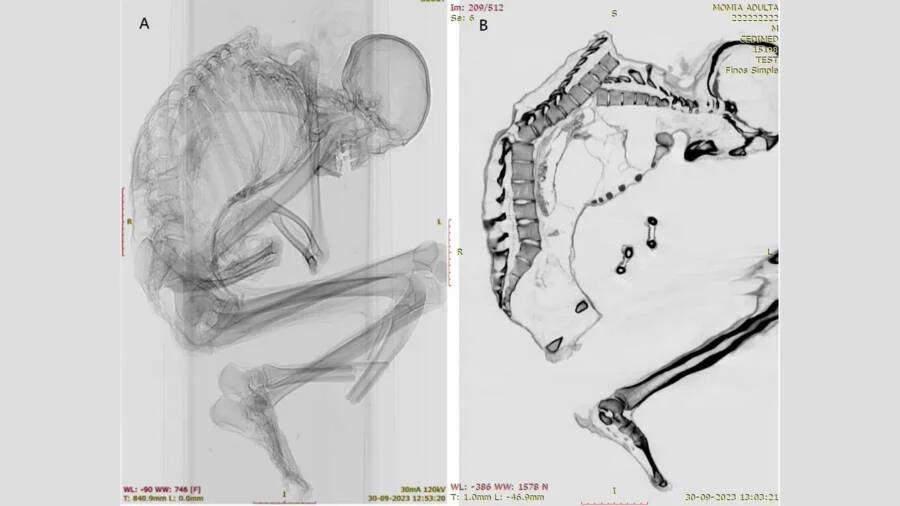

Michael Flores+FollowMedieval Knight’s Skull Reveals Rare SyndromeArchaeologists just uncovered a 600-year-old knight in Spain with a super rare condition—Crouzon syndrome. His skull was so unusually shaped that it’s the first adult case ever found in a medieval warrior! Despite his jaw issues and unique head shape, this guy still rode horses and fought in battles. Imagine living with that in the Middle Ages and still being a total badass! Science just keeps getting wilder. #Science #History #Archaeology141Share